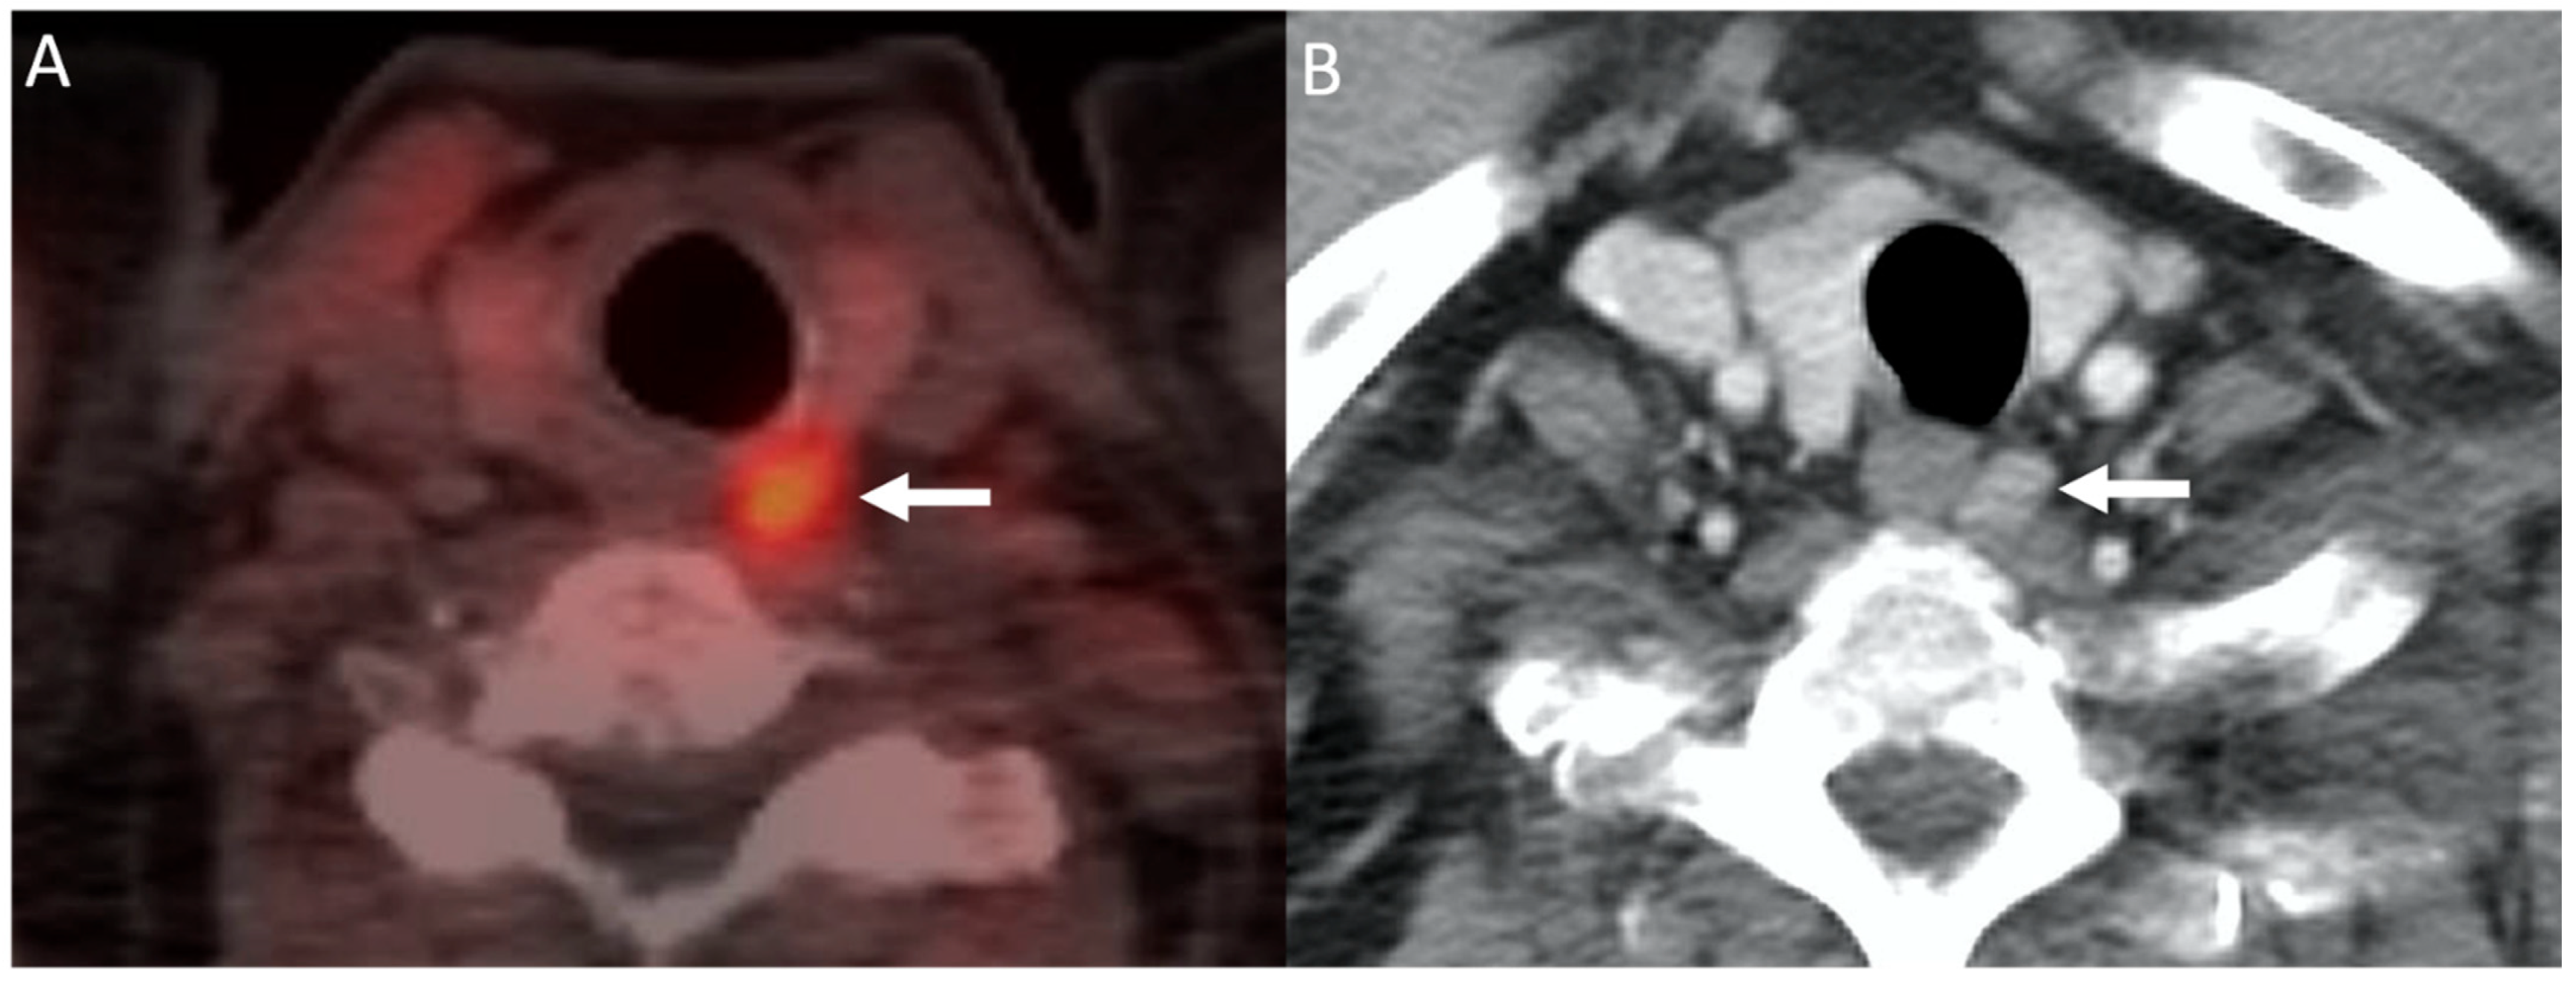

- Michaud, L.; Burgess, A.; Huchet, V.; Lefèvre, M.; Tassart, M.; Ohnona, J.; Kerrou, K.; Balogova, S.; Talbot, J.-N.; Périé, S. Is 18F-Fluorocholine-Positron Emission Tomography/Computerized Tomography a New Imaging Tool for Detecting Hyperfunctioning Parathyroid Glands in Primary or Secondary Hyperparathyroidism? J. Clin. Endocrinol. Metab. 2014, 99, 4531–4536. [Google Scholar] [CrossRef] [PubMed]

- Amadou, C.; Bera, G.; Ezziane, M.; Chami, L.; Delbot, T.; Rouxel, A.; Leban, M.; Herve, G.; Menegaux, F.; Leenhardt, L.; et al. 18F-Fluorocholine PET/CT and Parathyroid 4D Computed Tomography for Primary Hyperparathyroidism: The Challenge of Reoperative Patients. World J. Surg. 2019, 43, 1232–1242. [Google Scholar] [CrossRef] [PubMed]

- Treglia, G.; Piccardo, A.; Imperiale, A.; Strobel, K.; Kaufmann, P.A.; Prior, J.O.; Giovanella, L. Diagnostic performance of choline PET for detection of hyperfunctioning parathyroid glands in hyperparathyroidism: A systematic review and meta-analysis. Eur. J. Nucl. Med. Mol. Imaging 2019, 46, 751–765. [Google Scholar] [CrossRef]

- Kluijfhout, W.P.; Vorselaars, W.M.; Vriens, M.R.; Rinkes, I.H.B.; Valk, G.D.; De Keizer, B. Enabling minimal invasive parathyroidectomy for patients with primary hyperparathyroidism using Tc-99m-sestamibi SPECT–CT, ultrasound and first results of 18F-fluorocholine PET–CT. Eur. J. Radiol. 2015, 84, 1745–1751. [Google Scholar] [CrossRef]

- Fischli, S.; Suter-Widmer, I.; Nguyen, B.T.; Muller, W.; Metzger, J.; Strobel, K.; Grünig, H.; Henzen, C. The Significance of 18F-Fluorocholine-PET/CT as Localizing Imaging Technique in Patients with Primary Hyperparathyroidism and Negative Conventional Imaging. Front. Endocrinol. 2018, 8, 380. [Google Scholar] [CrossRef]